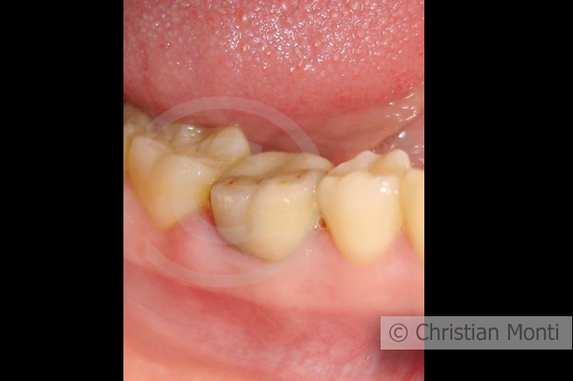

EDENTULIA SINGOLA

Impianto dilazionato in sostituzione di un molare inferiore